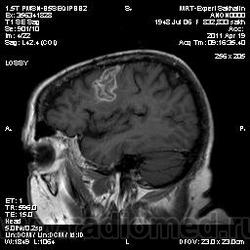

склоняюсь к кровизлиянию в левой теменной долей, начало перехода острой стадии в раннюю подострую( по периферии определяется повышение МРС по Т1 ВИ -метгемоглобин). Справа -старые кортикальные постишемческие глиозно-атрофические изменения. Контрастируется , вероятно за счет формирования участков ангионеогенза.

На фоне ДЭП изменений МР-картина ОНМК по ишемическому типу в бассейне ЛСМА с участками геморрагического пропитывания. Аналогичный участок но в более поздней фазе в задних конвнкситальных отделах правой теменной доли.

О.С., я согласен, что контрастирование нехарактерно для ОНМК, ведь в подострую стадию инфаркта наблюдается, как правило, гиральный тип усиления. Плюс, на ОНМК непохоже то, что поражено почти только белое вещество, а кора интактна. И потом, при такой локализации инфаркта обязательно должна быть яркая клиника, и уж никак не только "головная боль".

А средний мозг ?Там тоже очаги гиперинтенсивного по Т2сигнала.

Что касается снимочков мне кажется что зона патологического сигнала в левой гемисфере можно расценить как подострую стадию ОНМК с геморрагическим пропитыванием, справа как последствия ОНМК. При чем множественные очаги скорей всего как проявление ХМНК. И обязательно рекомендовать контрольное МРТ в динамике . Если это действительно ОНМК на фоне лечения отек уйдет и будет формированиться зона кистозно-глиозных изменений, а если отек будет нарастать значит надо думать о объемном процессе.

Скажите пожалуйста, а что с лобными полюсами полушарий?

Что касается лобных долей мне не хватает мр- изображения . Ну думаю это может быть связано с гиперостозом костей. Для уточнения можно назначить МСКТ.